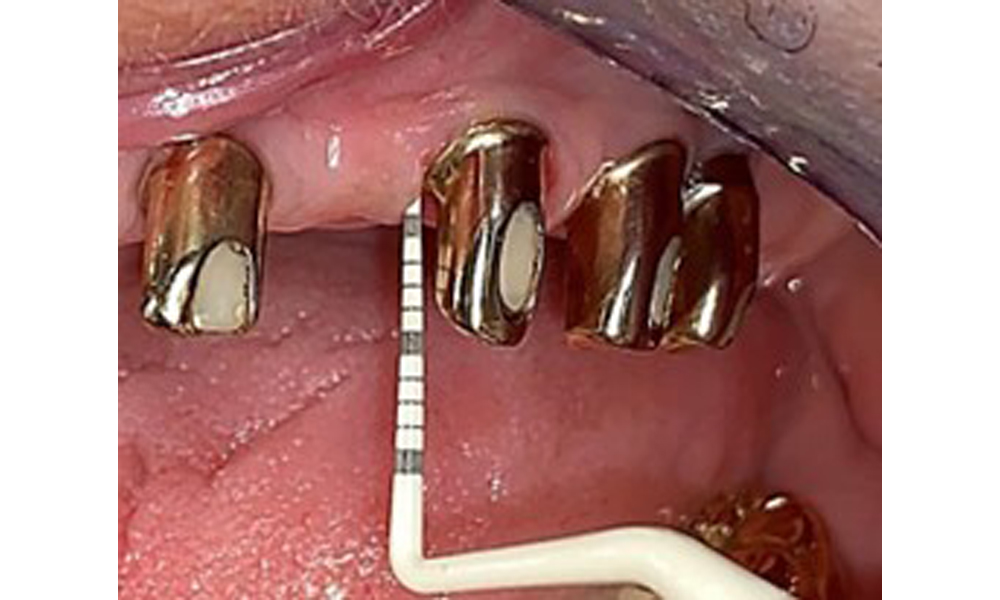

Occlusal view: Maxilla with tooth and implant-supported telescopic prostheses.

Fig. 2: Occlusal view: Maxilla with tooth and implant-supported telescopic prostheses

The dental findings are as follows: Combined removable implant and tooth-supported telescopic prostheses on implants 15, 13, 21, 23, 24, 25 and tooth 11 (Fig. 1, Fig. 2, Fig. 3). The patient was fitted with a fixed mandibular denture. Adequate bridges were present over 37 to 34 and 45 to 47 (Fig. 4), the crown margins were intact and there were no active caries. A composite filling with a marginal gap was present on tooth 43. There was mandibular gingival recession, exposing 1 to 3 mm of root surface. This also applies to 11.